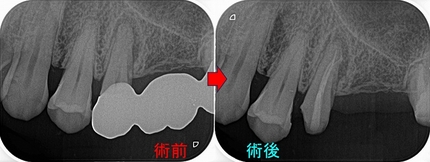

このケースの患者さんが他の歯の治療で来院されたのでレントゲンを撮らせてもらいました。

骨はしっかり出来てくれています!